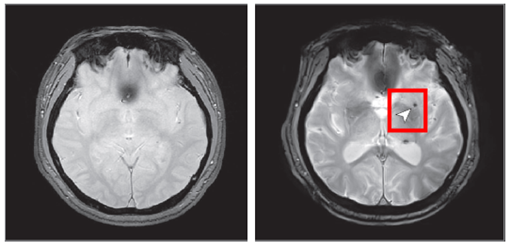

중간 수준 수면무호흡증도 뇌 미세출혈 위험 2배

위험을 약 2배 높인다는 한국인 대상 연구결과가 나왔다. 질병관리청 국립보건연구원은

중장년층을 대상으로 수면무호흡증과 뇌 미세출혈 위험 사이의 관계를 확인했다고 3일 밝혔다. 연구결과는 10월 28일(현지시간) 국제학술지 '미국의사협회지(JAMA) 네트워크 오픈'에 공개됐다. ... ...